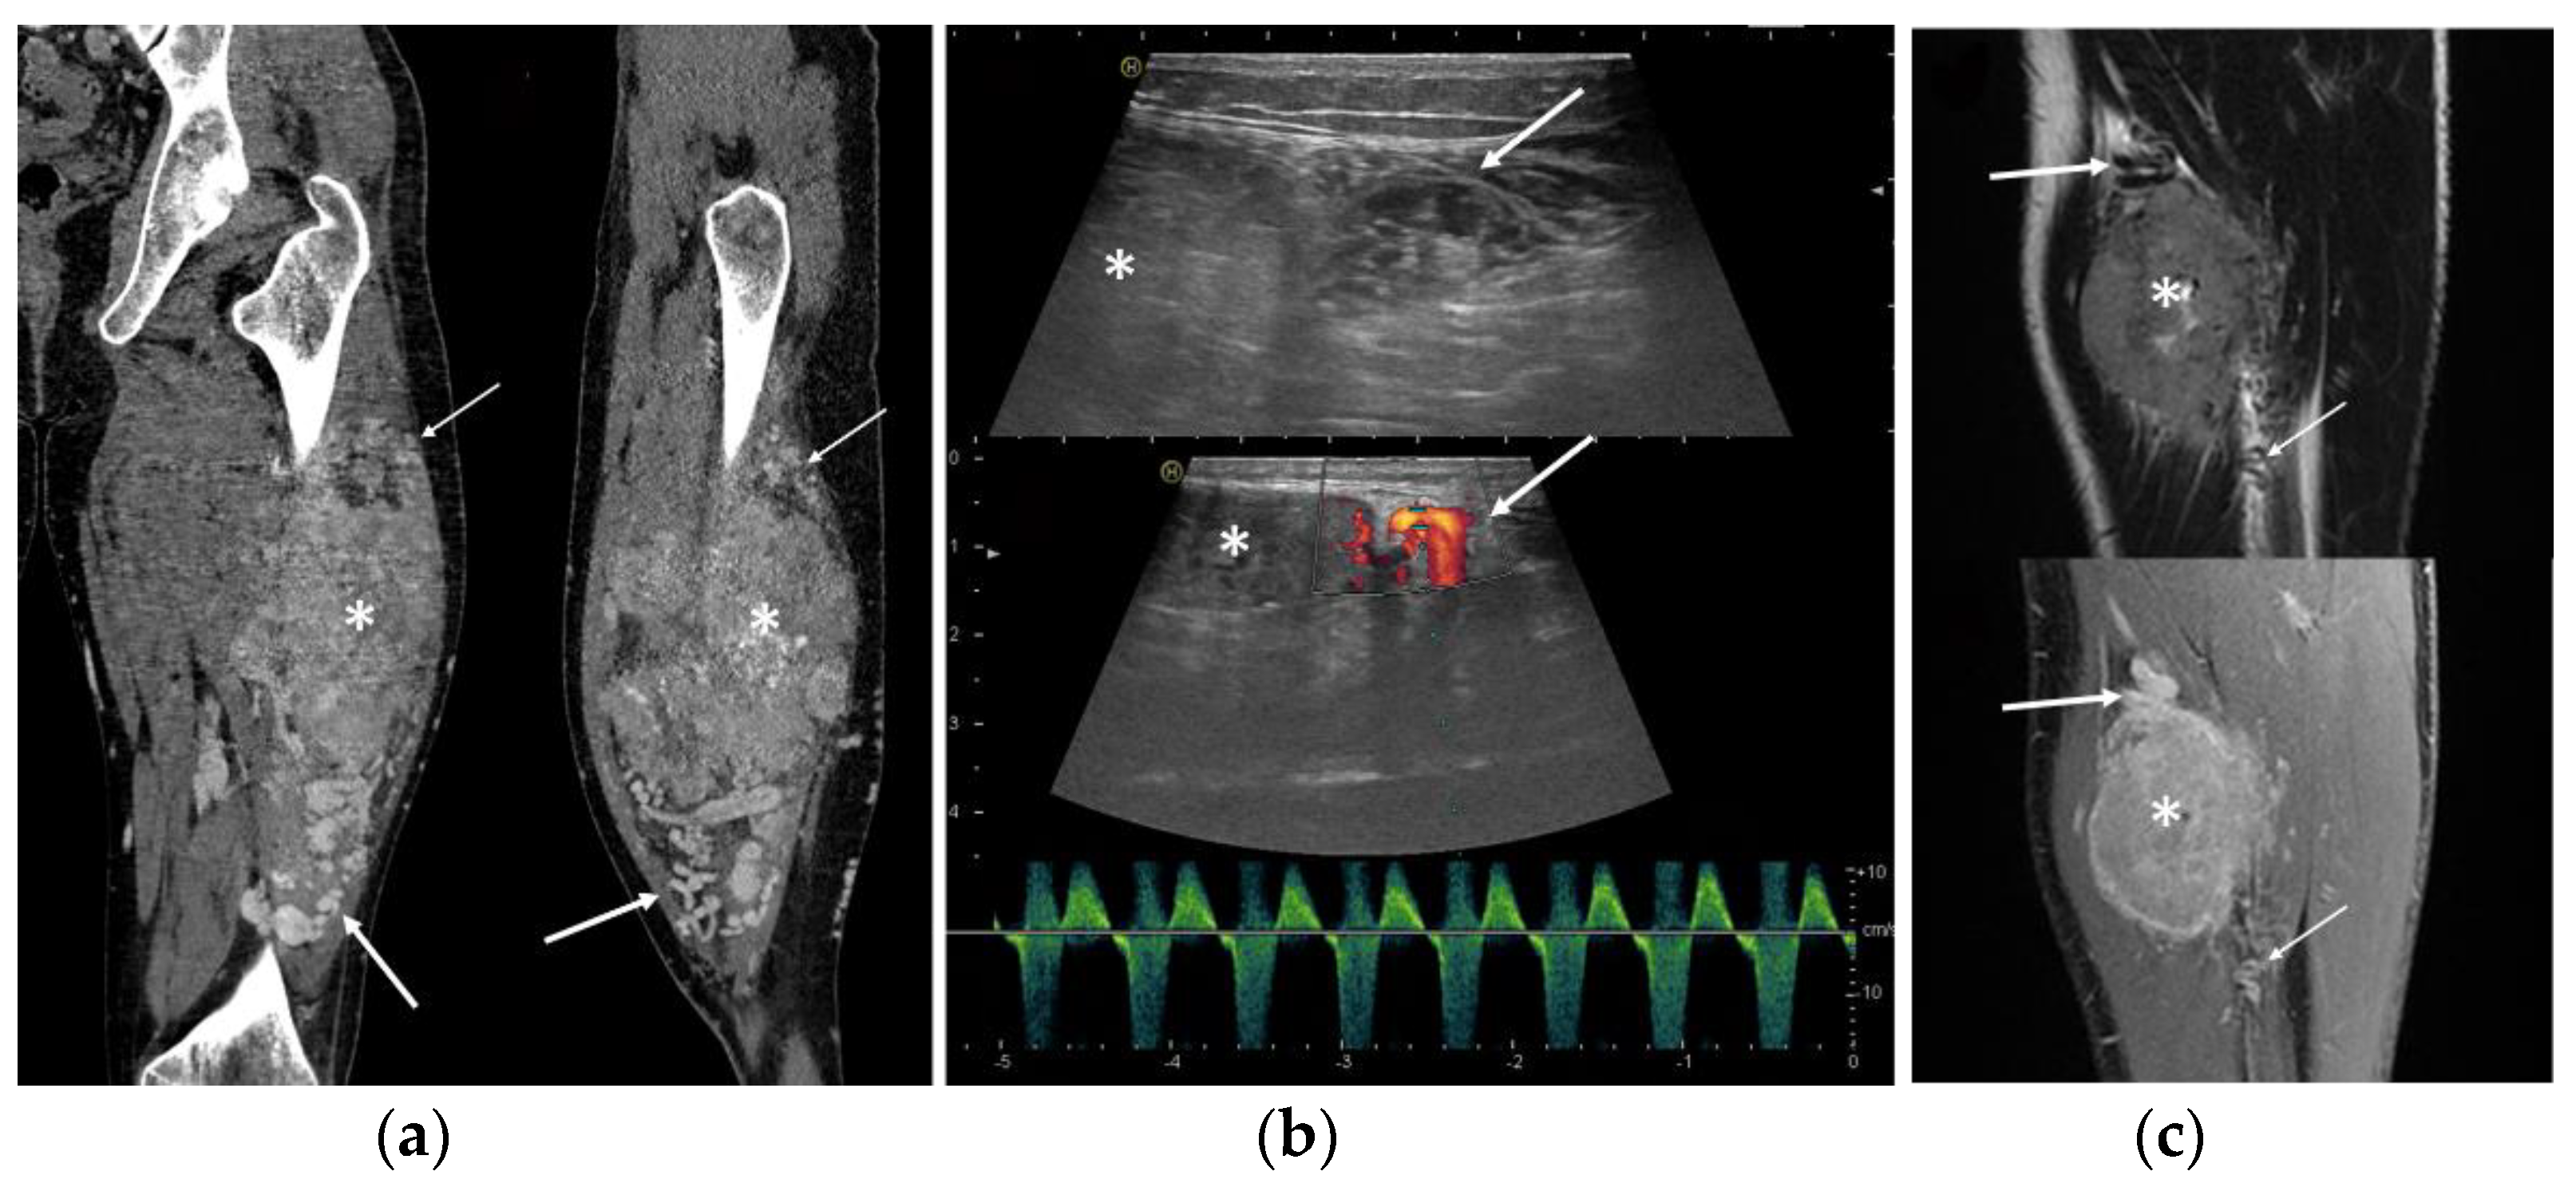

3.3. Ultrasound Features

3.4. MRI Features

3.5. CT Features

- Deep location

- Presence of peritumoral feeding vessels

- Inhomogeneous, mainly hypoechoic US pattern with strong internal vascularization at Color-Doppler evaluation

- Slight hyperintense MRI signal on T1-WI and a moderately inhomogeneous hyperintense signal on T2-WI

- MRI flow voids on fluid-sensitive sequences

- MRI peritumoral edema

- Slight low density and inhomogeneity on unenhanced CT